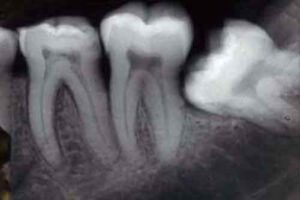

Le persone che hanno effettuato frequenti radiografie ai denti hanno maggiori possibilta' di sviluppare un tumore al cervello. In particolare,...